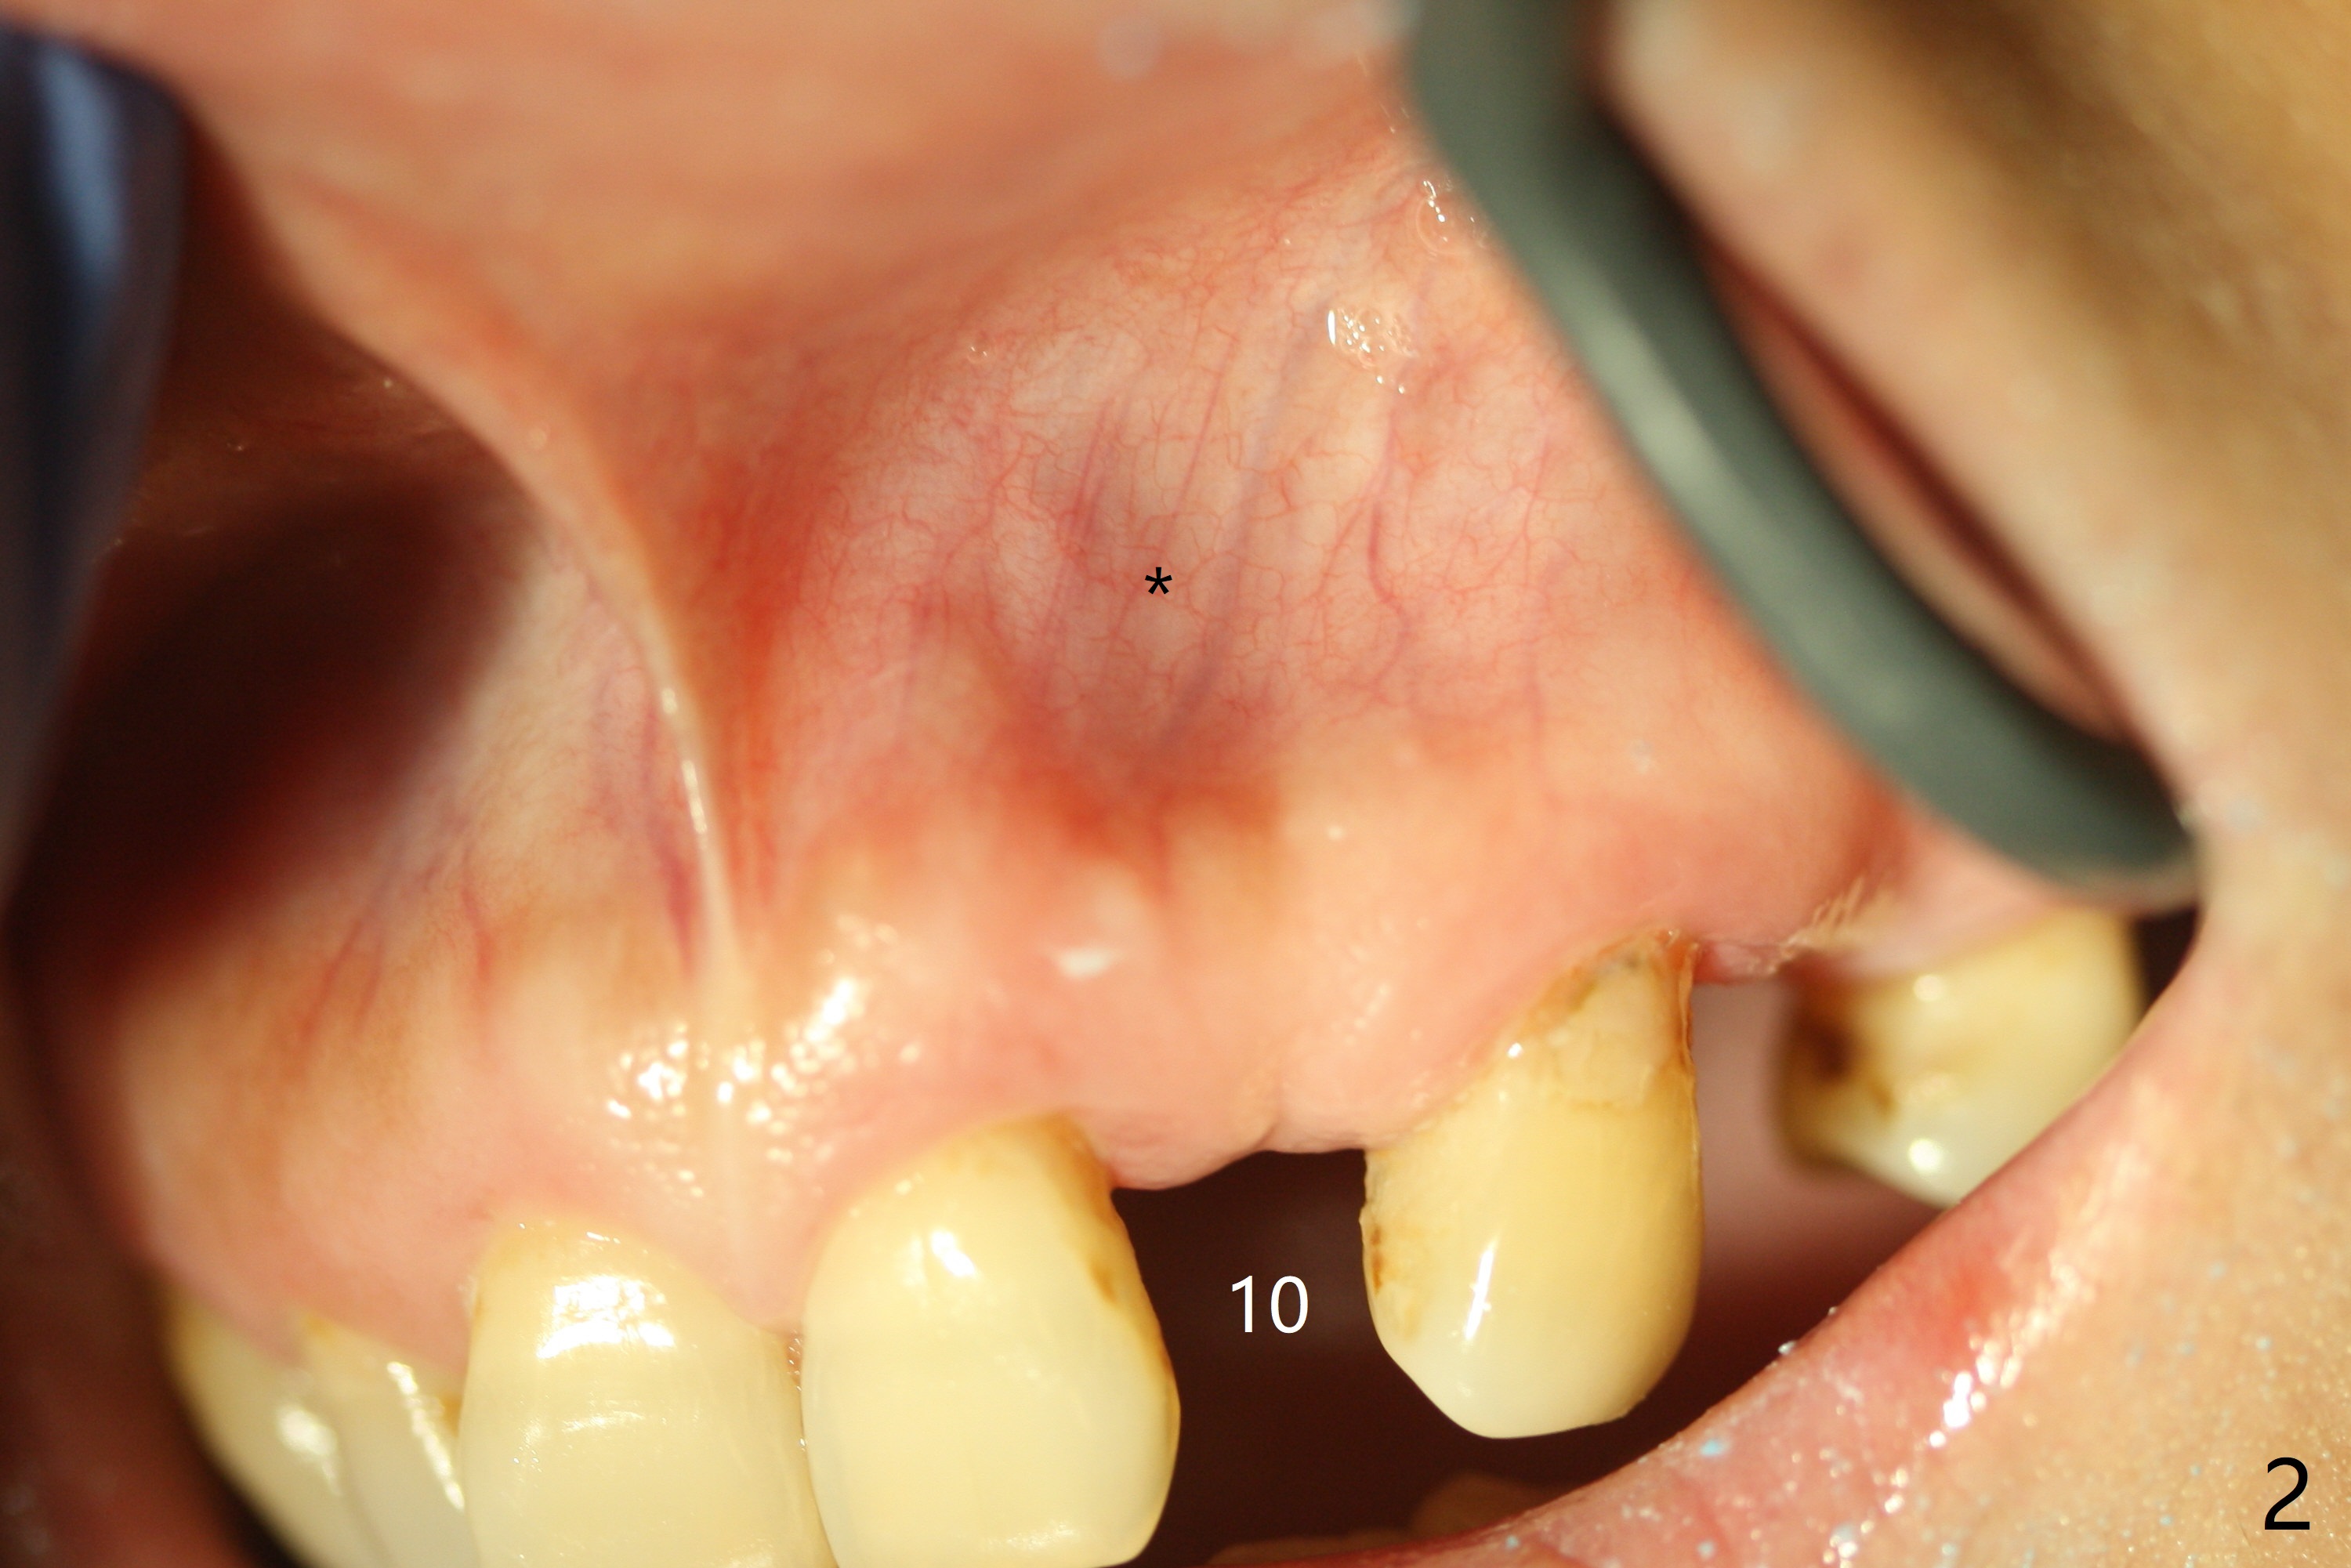

The patient has gummy smile (Fig.1).  The edentulous ridge at #10 has buccal concavity (Fig.2 *).  The surgical guide fits well without #9 distal trimming.  With 34 mg Xylocaine and 17 mcg Epinephrine infiltration at #10 and 12, the patient feels pain when 2.2 (in fact 1.9) x8.5 mm drill is being used.  When Septocaine is added, the osteotomy at #10 is found distal.  Out of curiosity, PA is taken with 2.2x10 mm drill in place; its trajectory seems satisfactory (Fig.3).  When a 2.5x13 mm 1-piece implant is placed free hand, it deviates palatal, which is confirmed with incision after addition of 34 mg Xylocaine and 34 mcg Epinephrine.  A new osteotomy is created by S-Mini Kit buccal to the previous one.  With Lindamann bur to adjust the position of the new osteotomy twice, the last drill (2.0 mm) apparently starts to perforate the apical portion of the buccal plate.  The perforation seems to enlarge when the mini implant is re-placed (Fig.4, 8 (green area) <30 Ncm).  With Vanilla graft (Fig.8 pink circles) and abutment height adjustment (Fig.4), a provisional is fabricated with occlusal clearance.  There are two reasons for failure of the surgical guide: failure to trim the tooth #9 distal (minor palatal guide displacement, Fig.5) and deflection of pointed drill and 2.2 mm drills over the hard palatal plate slope (Fig.6).  To avoid this complication, the pointed drill should be done free hand initially, after incision and obliquely (Fig.7).  The guide is placed to finish the rest of osteotomy if deem to be appropriate.